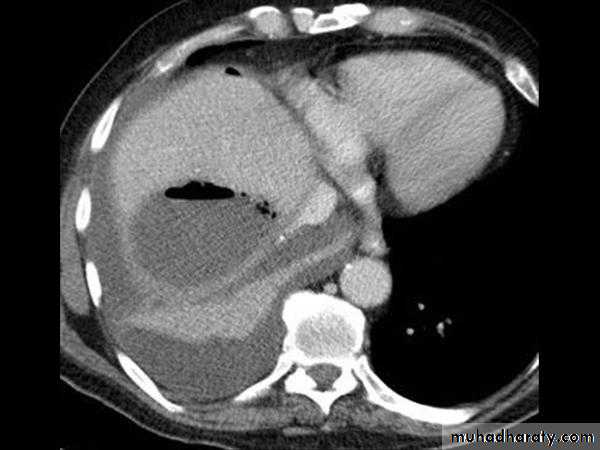

Liver abscess:

CT scan

Malignant neoplasms: